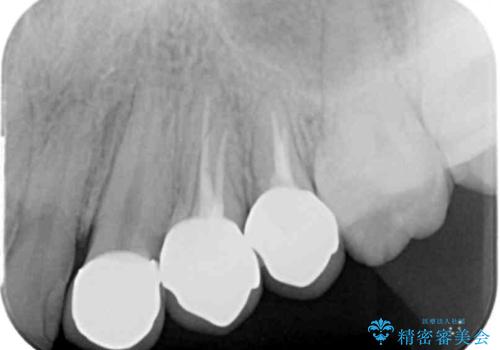

- 47.3万円(仮歯×3・ファイバーコア・ジルコニアクラウン×3・部分小矯正)費用は治療当時の料金となります

小矯正を行い深い虫歯を改善した後は、小手術を行うことで歯ぐき・周囲歯槽骨の状態を整えることでより安定した歯周環境を得ることができます。